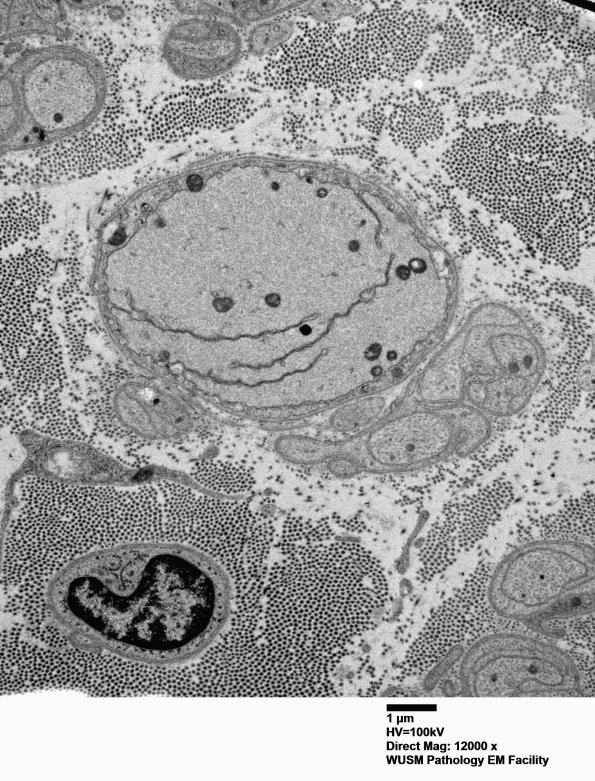

A large demyelinated axon exhibits unusual invagination of the axolemma, a result I have seen in both artifactual axon crush or in a degenerating/demyelinated/remyelinated axon. (electron micrograph)